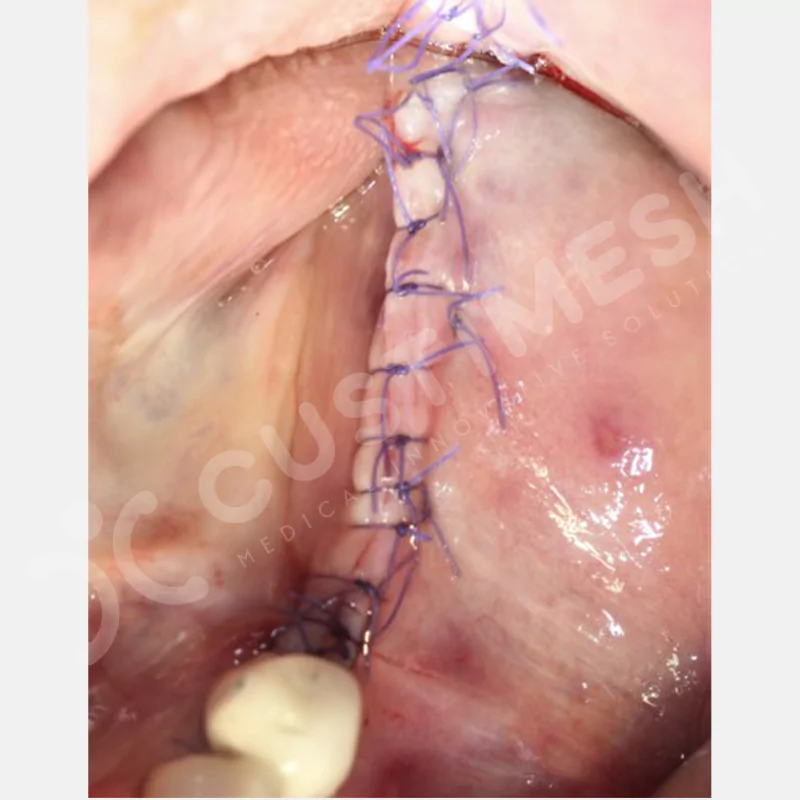

VAKA 1

VAKA 2

VAKA 3